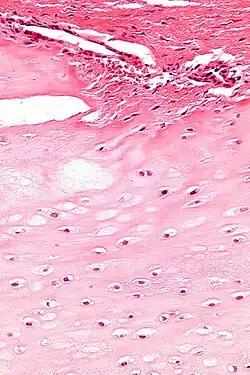

Micrograph of an enchondroma. H&E stain.

Enchondroma is a type of benign bone tumor that originates from cartilage. The exact etiology of it is not known. An enchondroma most often affects the cartilage that lines the inside of the bones. The bones most often involved with this benign tumor are the miniature long bones of the hands and feet. It may, however, also involve other bones such as the femur, humerus, or tibia. While it may affect an individual at any age, it is most common in adulthood. The occurrence between males and females is equal. It is not very likely that the enchondroma will grow back in the same spot; the rate is less than ten percent.